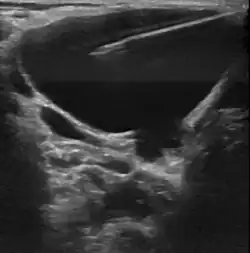

Пороки развития лимфатических сосудов в области головы и шеи чаще всего определяются при рождении или в первые годы жизни ребёнка, в возрасте до одного года в 60-80 % случаев[6]. Основными методами визуализации лимфатической мальформации являются ультразвуковое исследование (УЗИ) и магнитно-резонансная томография (МРТ). Данные исследования позволяют определить площадь и объём патологических тканей, размеры кист, топографию образования.

Появление лимфатической мальформации характеризуется наличием объемного образования, которое расположено под кожей, имеющее мягкую консистенцию. При пальпации оно не смещается и безболезненно, температура образования не отличается от других участков кожного покрова (нет гипертермии), довольно часто определяется симптом флюктуации. Для каждого варианта лимфатической мальформации присуще различные клинические проявления.